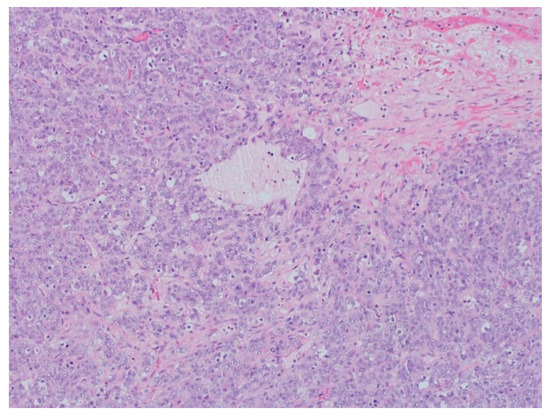

2. Case Report